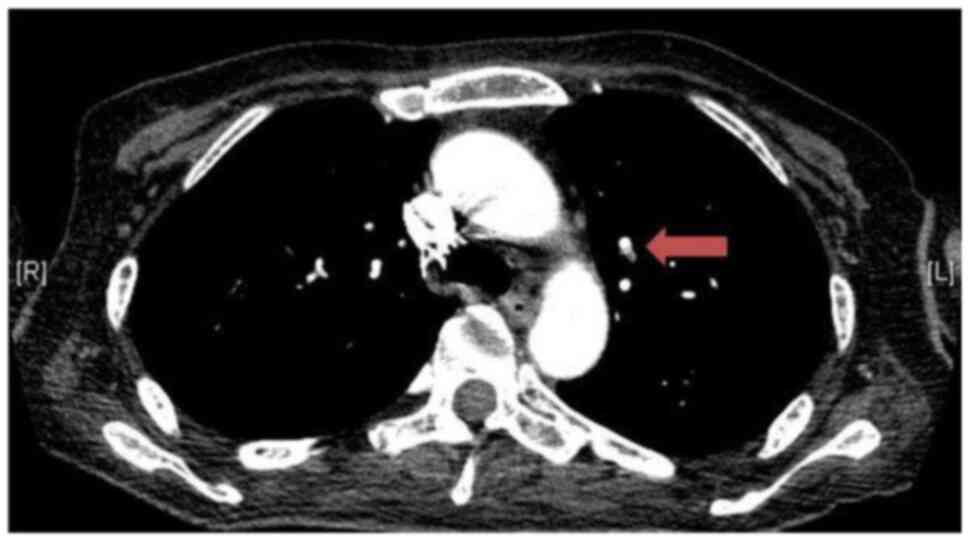

crackling breath sounds. A chest X-ray and subsequent thorax

computed tomography (CT) scan documented pulmonary microembolism

(Fig. 1), while an abdomen CT scan